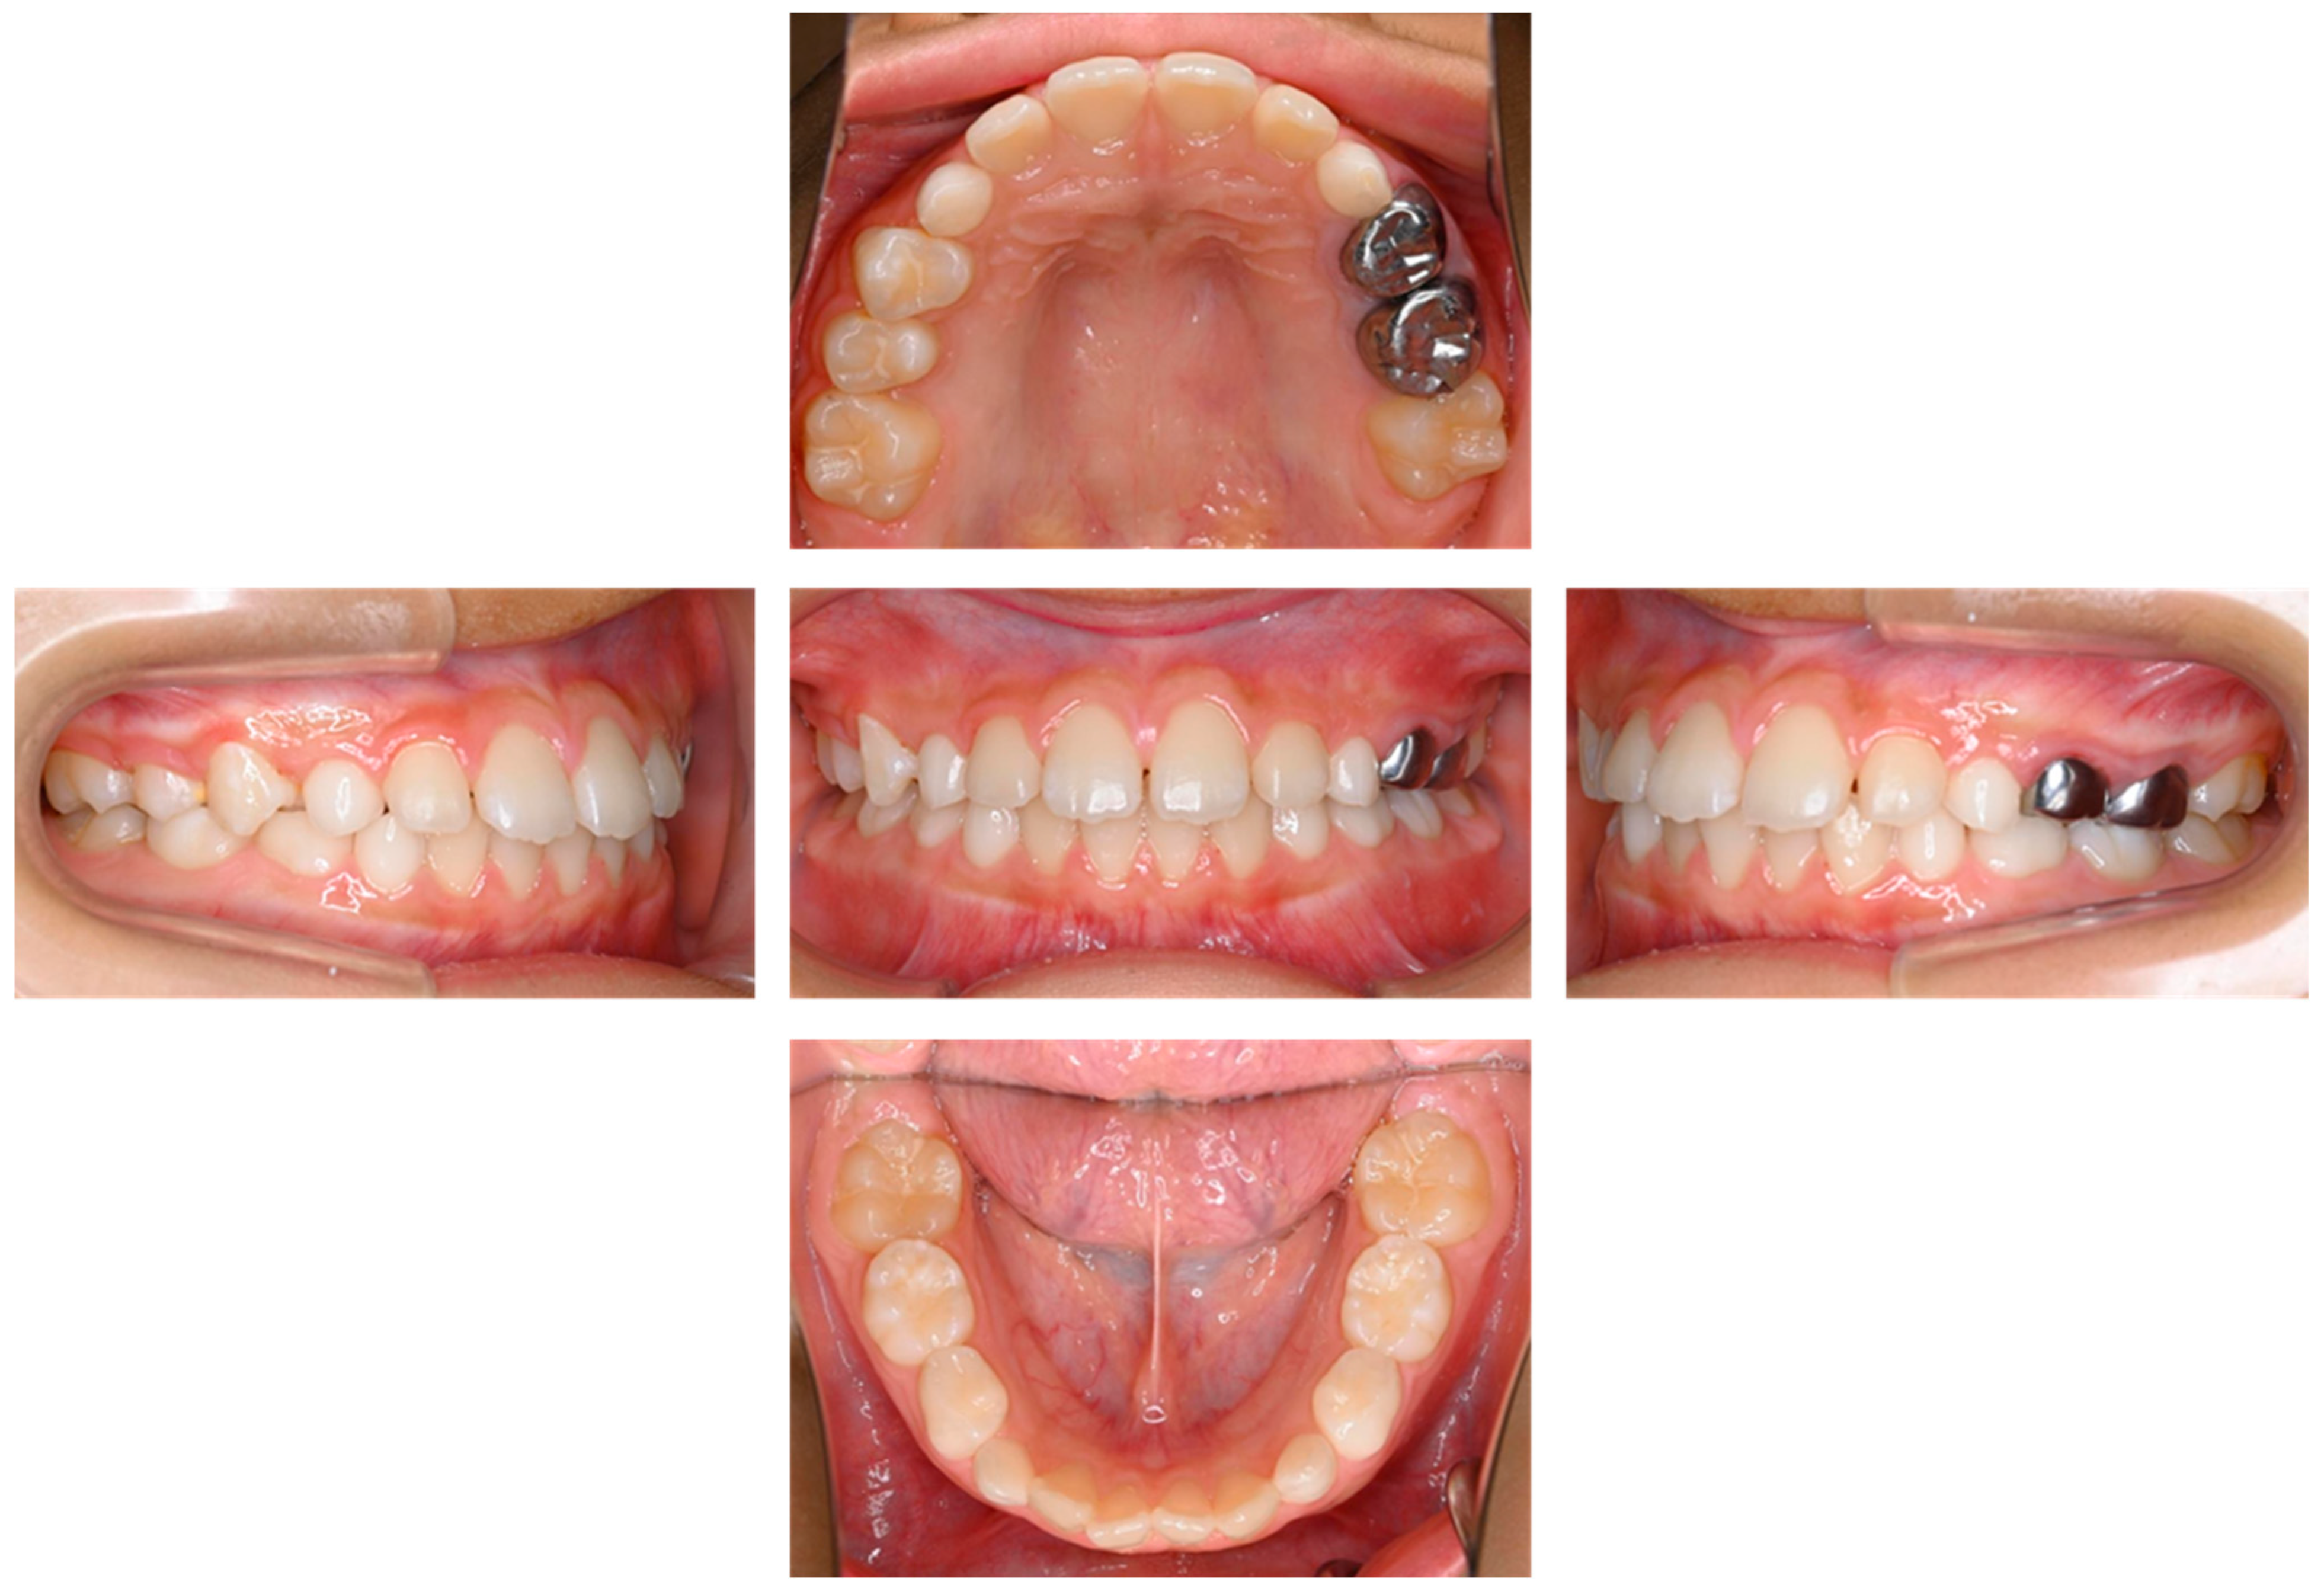

| Present case | #55 | Mesio-buccal canal | Reamer | 17 months | Enamel hypoplasia |